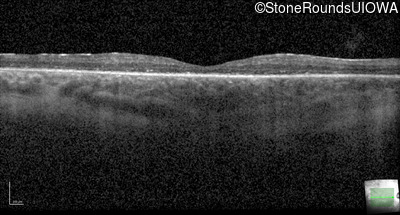

Optical Coherence Tomography - Left - 20/50

Exemplar / OCT Stack

OCT Stack